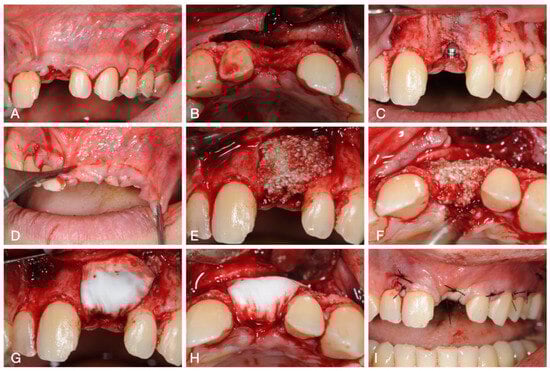

2. Case Report